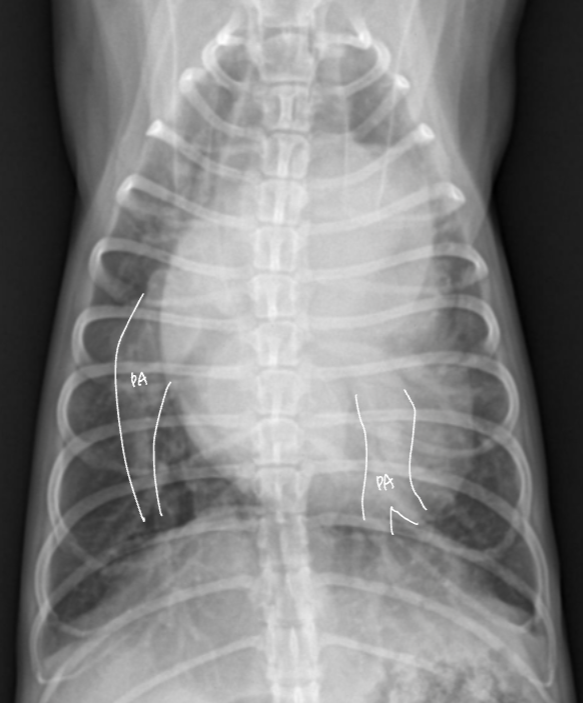

| LA enlargement |

| - wing sign, backpack sign - bow-legged cowboy sign - double wall sign HCM์์ ์ ๊ด์ฐฐ๋๋ค. |

![]() ![]() |